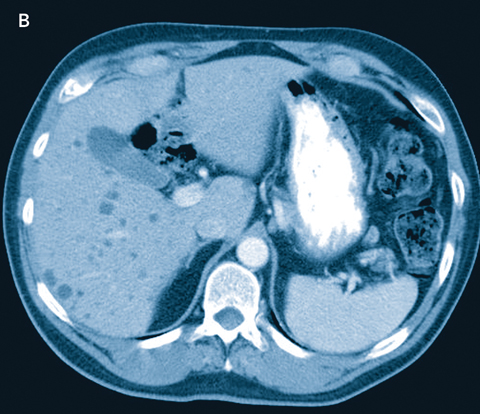

A 57-year-old man had a colonoscopy which revealed a partially obstructing polyp in the rectum. Biopsy revealed an adenocarcinoma. A computed tomography scan of the abdomen revealed multiple low-attenuation lesions diffusely throughout the liver (Box). Differential considerations included multiple small hepatic cysts, Caroli’s disease, microabscesses and metastases. The patient had a low anterior resection for his rectal tumour and wedge biopsy of the liver. Macroscopically, there were multiple 2–3 mm white nodular lesions throughout the liver, with the macroscopic appearance of diffuse liver metastases. Pathology of the liver biopsy revealed von Meyenberg complexes.